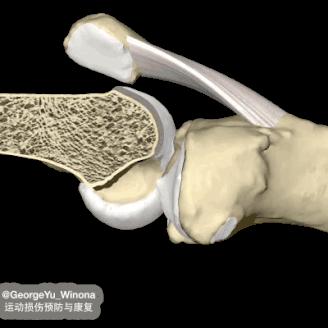

了解疾病前,先来了解膝关节的正常结构。

股骨、胫骨和髌骨共同构成膝关节的骨性结构,在互相接触的关节面,都覆盖一层光滑的关节软骨,同时股骨和胫骨之间有半月板,关节腔内有关节液。

三者相互配合润滑关节、减少摩擦,在运动中缓冲压力,共同维护关节的正常功能和状态。